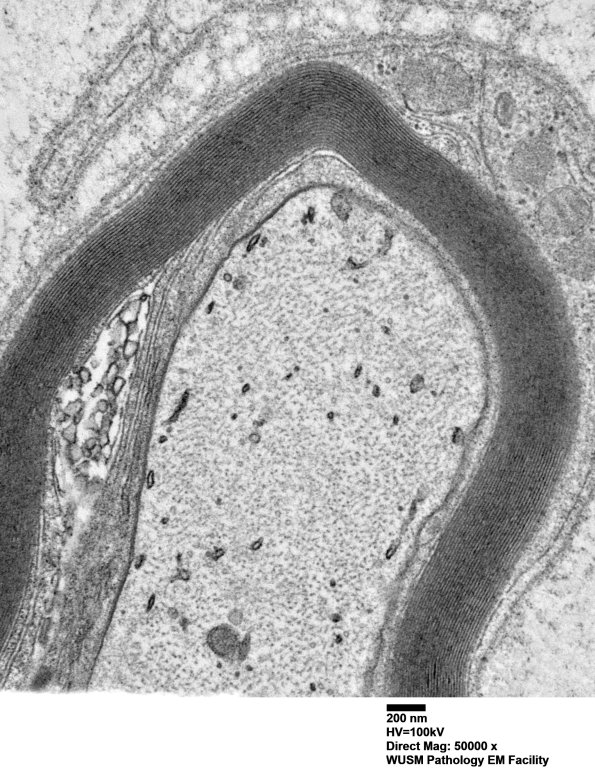

Washington University Experience | PERIPHERAL NEUROPATHY | 13 POEMS SYNDROME | 1C3B (Case 1) Sural_052 - Copy

1C3B (Case 1) Sural_052 - Copy

Higher magnification of image #1C3A. (electron micrograph)